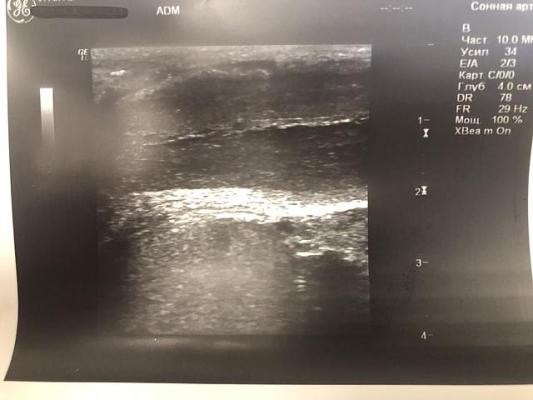

При УЗИ полового члена: определяются гиперэхогенные включения с чёткой эхо-тенью в проксимальной трети дорзально 3х1.5 мм и между кавернозными телами 3.3х2 мм (фрагменты исходной бляшки), дистально - два включения 2х1 мм дорзально и три от 1.5 до 3 мм между кавернозными телами.